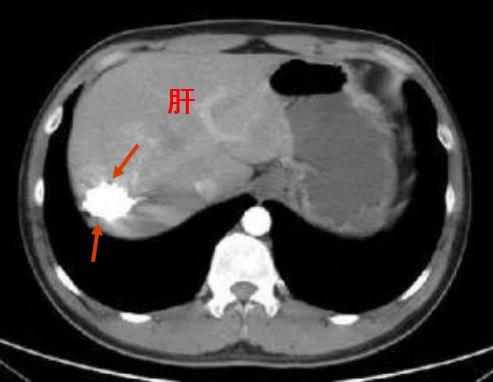

介入疗法的出现,在很大程度上改变了很多疾病的诊疗模式,但并非与传统疗法相冲突,更不可能造成“颠覆”的结局,而是可以很好地进行协同。在同一病例的不同阶段,内科、外科、介入疗法通常可以联合应用,取长补短。举个例子,发现有个恶性肿瘤,由于体积巨大,并不具备切除条件,这在以往可能就是“不治之症”,但如今却可先做介入,进行“降期”,为手术切除创造条件。有些手术后残存的肿瘤,也可结合术后介入等手段强化治疗,各种疗法的联系紧密得很呢!

介入杀灭大部肿瘤后,为手术切除创造条件